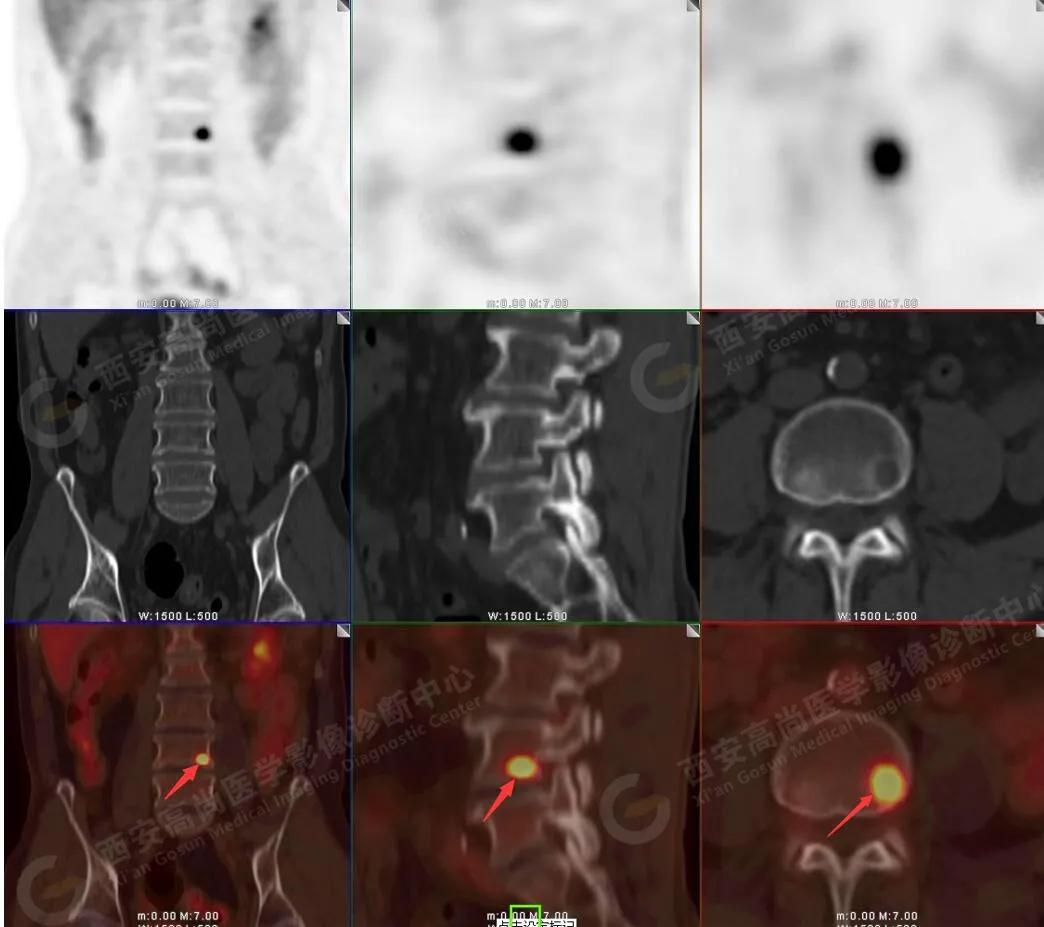

腰4椎体骨转移瘤

5.腰4椎体左侧缘溶骨性骨质破坏,FDG代谢异常增高,考虑骨转移瘤。

髂骨多发骨转移

左侧髋臼多发骨转移

脊柱多发骨转移